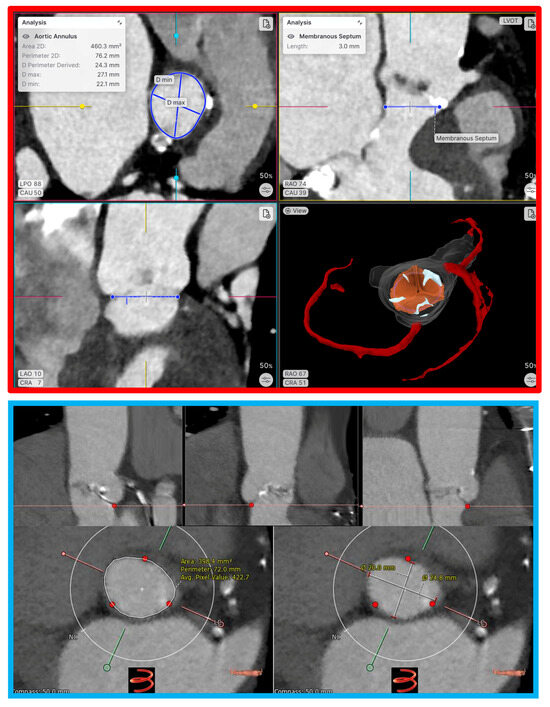

4.1. TAVI

4.1.1. Optimal Sizing

4.1.6. Prediction of Conduction Disturbances